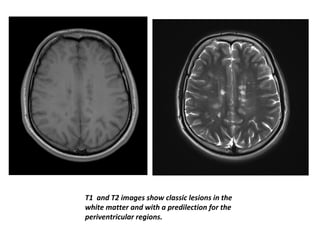

• MS lesions are frequently situated in the

periventricular white matter, internal capsule,

corpus callosum, pons, cerebellum, medulla but

may be found throughout the myelinated white

matter and within gray matter.

• The demyelination plaque is characterised by

increase in water content, following BBB

disruption, inflammatory perivascular reaction

and myelin loss.

• The focal increase in water content produces a

hyperintense signal in T2 weighted images

within the hypointense background of the white

matter.

• Lesions typically appear iso to hypointense on T1

and hyperintense on T2.

T1 and T2 images show classic lesions in the

white matter and with a predilection for the

periventricular regions.